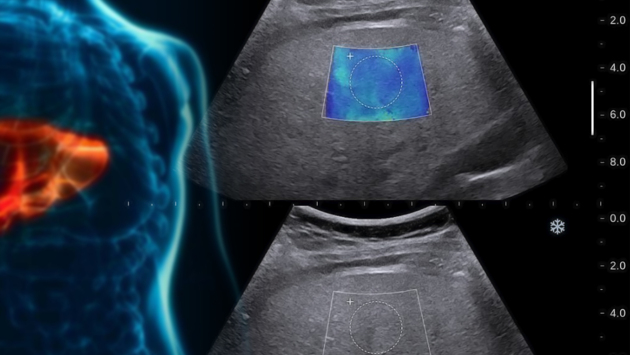

Ученые из Санкт-Петербургского политехнического университета Петра Великого и Российского научного центра радиологии и хирургических технологий разработали экспериментальную оптическую установку для диагностики заболеваний печени. Основные преимущества устройства перед существующими приборами — экономичность, простота использования и быстрое представление результатов в реальном времени. Работа опубликована в журнале Diagnostics. Для определения функциональных резервов печени исследователи обычно используют индоцианин зеленый. Этот нетоксичный краситель хорошо связывается с белками крови и через кровоток доставляется в печень. Краситель внутривенно вводят пациенту, а затем наблюдают, за какое время печень выведет его из организма. Концентрацию индоцианина зеленого в крови измеряют с помощью оптической установки. Созданный учеными прибор работает на основе измерения оптической плотности. Серийные образцы сыворотки крови пациента последовательно помещаются в прибор, на него подается свет, и с помощью детектора ученые фиксируют интенсивность рассеянного излучения, которое проходит через образец. Устройство подключено к компьютеру, и результат выдается мгновенно. От концентрации индоцианина зеленого в крови зависит, насколько сильно краситель поглощает свет. Чем ниже отношение начальной и конечной концентраций, тем больше поражены клетки печени. По степени выведения красителя врач может оценивать функциональные резервы печени и строить дальнейший план лечения. «Сейчас для проведения такой диагностики используется спектрофотометр — большой и дорогостоящий прибор. Мы подобрали менее дорогой источник возбуждения, модернизировали фотоприемную часть и блок съема сигнала», — отмечает один из авторов работы, сотрудница Высшей школы прикладной физики и космических технологий СПбПУ Екатерина Савченко. Ученые провели сравнительный анализ работы спектрофотометра и экспериментальной установки, статистически результаты оказались очень близки. Сейчас исследователи работают над неинвазивным применением данного метода. В нем будут исследоваться не образцы плазмы пациента, а количество поглощенного света красителем в потоке крови. Для этого ученым предстоит создать алгоритм обработки сигнала и разработать оптимальную конструкцию оптических датчиков пульсовой волны для пальца и ушной раковины. Последние будут созданы на 3D-принтере. Если устройство докажет свою эффективность, его будут внедрять в медицинскую практику. Понравился материал? Добавьте Indicator.Ru в «Мои источники» Яндекс.Новостей и читайте нас чаще. Пресс-релизы о научных исследованиях, информацию о последних вышедших научных статьях и анонсы конференций, а также данные о выигранных грантах и премиях присылайте на адрес science@indicator.ru.